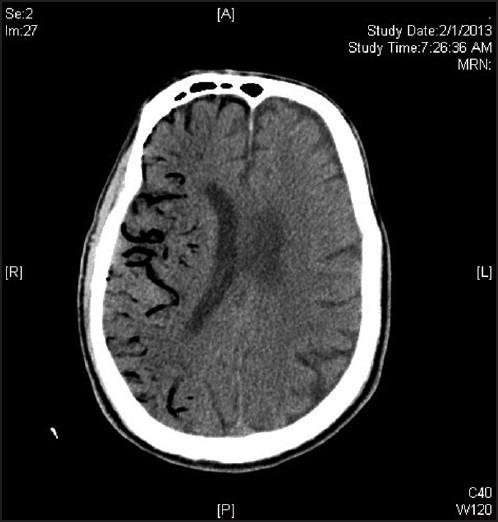

Air embolism is a preventable, often undiagnosed but potentially treatable cause of ischemic stroke with a high morbidity and mortality. It is usually iatrogenic ocurring especially in patients in ICU setting. We describe the case and neuroimaging of a patient with ischaemic stroke due to air embolism during manipulation of central venous line. We also review the literature with respect to aetiology, incidence pathophysiology, diagnosis, and treatment options for venous and air embolism. Cerebral air embolism should be considered in patients with sudden neurological deterioration after central venous or arterial manipulations or certain neurological procedures. Prevention, as well as early diagnosis and management, may reduce morbidity and mortality.

空气栓塞是缺血性卒中可预防、常未被诊断但可能可治疗的病因,具有高发病率和死亡率。它通常是医源性的,尤其发生在重症监护病房的患者中。我们描述了一例在中心静脉导管操作过程中因空气栓塞导致缺血性卒中患者的病例及神经影像学表现。我们还回顾了关于静脉和空气栓塞的病因、发病率、病理生理学、诊断及治疗选择的文献。对于在中心静脉或动脉操作或某些神经手术后突然出现神经功能恶化的患者,应考虑脑空气栓塞。预防以及早期诊断和管理可能会降低发病率和死亡率。